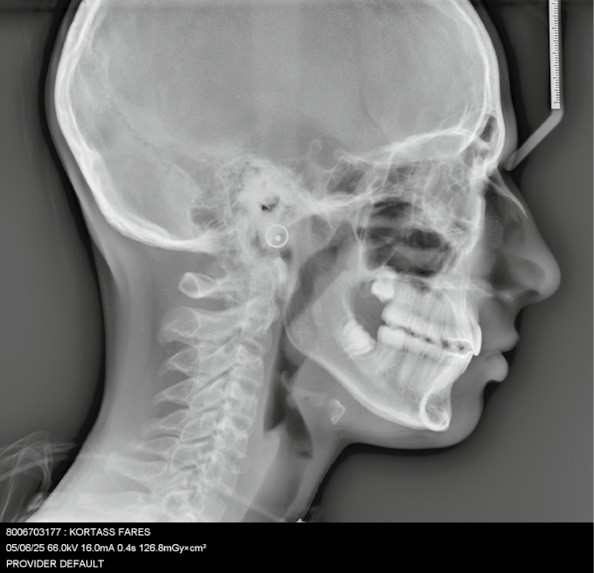

Sur le plan squelettique : Classe II, schéma hypodivergent (fig. 1c). Sur le plan fonctionnel : aucune dysfonction ni parafonction.